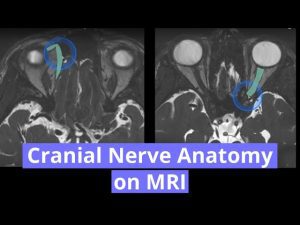

- This is a case of neurosarcodosis with pachymeningial involvement of the right tentorium. There was suspected involvement of the trochlear nerve (CN IV) in this region with resulting atrophy of the right superior oblique muscle.

- The trochlear nerve is the only cranial nerve to decussate. After decussating in the superior medullary velum it courses anterolaterally within the ambient cistern and along the free edge of the tentorium. It then travels in the lateral wall of the cavernous sinus and enters the orbit via the superior orbital fissure. It innervates the superior oblique muscle. It does not course in Dorrelo’s canal (CN VI does).